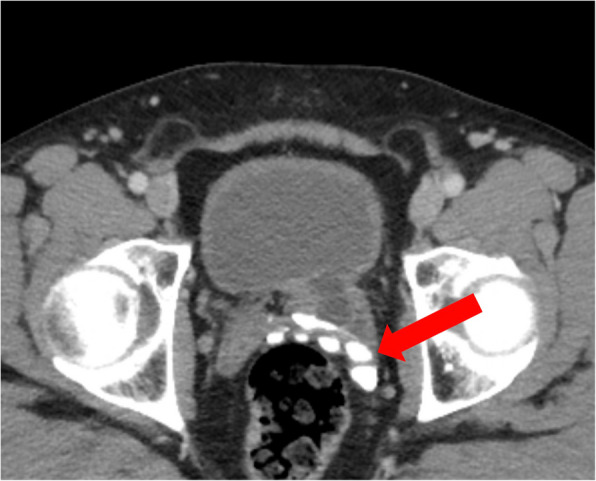

简介和重要性:“先天性肾脏和尿路异常”(CAKUT)是一种异质性和罕见的影响尿路的疾病。尽管超声广泛可用,先天性尿路畸形的诊断往往是在成年。因此,在成像调查中,CAKUT通常是偶然发现的。本病例报告首次描述了同时手术治疗CAKUT和保留神经的前列腺切除术,表明合并手术并不存在缺点,并且在神经安全控制下仍然可以进行成功的保留神经的根治性前列腺切除术。病例介绍:在这个报告中,我们描述了一个前列腺癌患者,他偶然发现左侧CAKUT,包括肾发育不全,输尿管膨出和膀胱憩室。患者同时行保留神经的根治性前列腺切除术、输尿管切除术和憩室切除术。术后第10天拔管后,患者尿控良好(24 h尿垫试验6gr,排尿量450 ml,无残尿)。病理检查显示pT2c pN0 (0/5) R0, GS 3 + 4 = 7a前列腺腺癌。患者对手术及其结果表示高度满意。结论:该病例首次表明,结合上、下泌尿生殖道的复杂手术,考虑肿瘤因素,可以安全地进行,而不会影响早期功能或早期肿瘤预后。

INTRODUCTION AND IMPORTANCE: "Congenital anomalies of the kidney and urinary tract" (CAKUT) represent a heterogeneous and rare group of disorders affecting the urinary tract. Despite the widespread availability of ultrasound, the diagnosis of congenital urinary tract malformations is often made in adulthood. As a result, CAKUT are typically incidental findings during imaging investigations. This case report represents the first description of a simultaneous surgical therapy of CAKUT and nerve-sparing-prostatectomy, demonstrating that concomitant surgery does not present disadvantages and that a successful nerve-sparing radical prostatectomy can still be performed under NeuroSAFE control. CASE PRESENTATION: In this report, we describe a patient with prostate adenocarcinoma who had an incidental finding of left-sided CAKUT, including kidney aplasia, ureterocele, and bladder diverticulum. The patient underwent a simultaneous nerve-sparing radical prostatectomy, ureterectomy, and diverticulectomy. After catheter removal on day 10 after surgery, the patient demonstrated adequate continence (6gr in 24 h pad test, 450 ml voiding volume, no residual urine). The pathological examination revealed a pT2c pN0 (0/5) R0, GS 3 + 4 = 7a adenocarcinoma of the prostate. The patient expressed high satisfaction with the surgery and its outcomes. CONCLUSION: This case demonstrates for the first time that a combined approach to complex surgeries of both the upper and lower genitourinary tracts, addressing oncological considerations, can be performed safely without compromising early functional or early oncological outcomes.